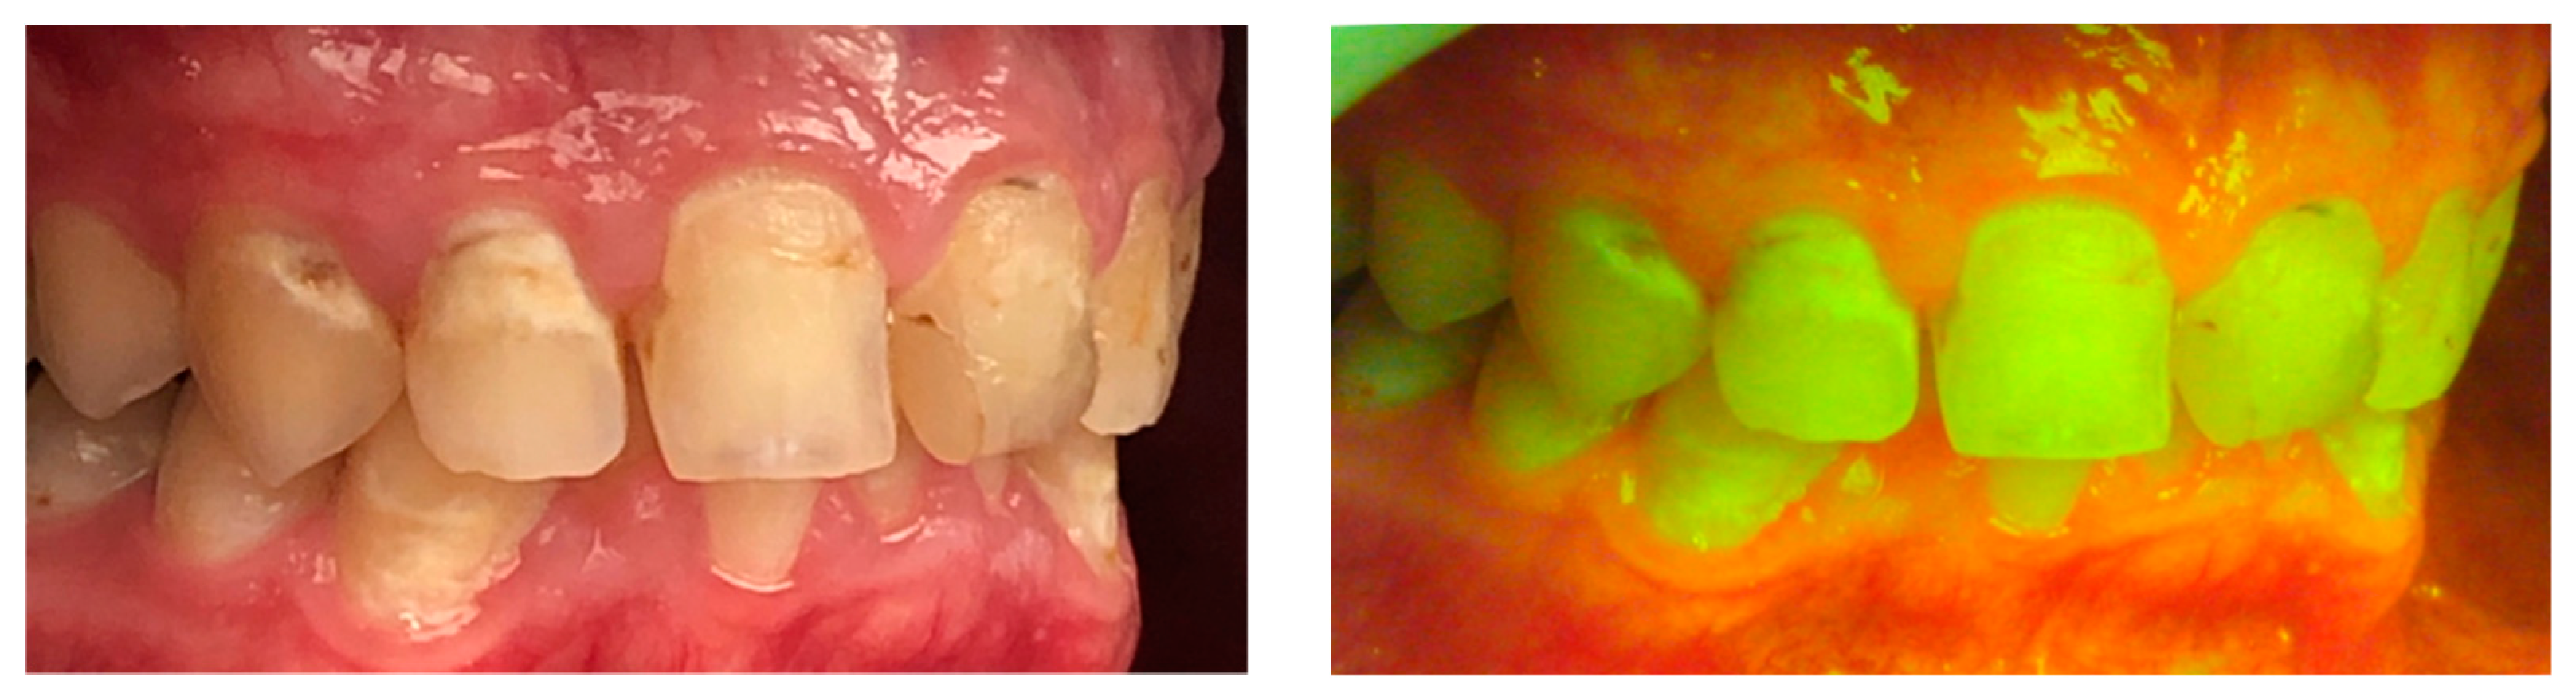

2. Hygiene Motivation and Monitoring during Treatment

- Steier, L. Reveal: Fluorescence Enhanced Theragnosis by Designs for Vision. Eur. J. Dent. 2020, 14, 186–188. [Google Scholar] [CrossRef] [PubMed] [Green Version]